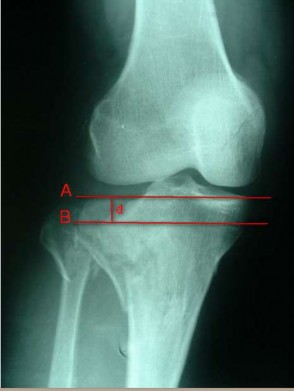

Độ lún mâm chày được xác định theo các bước:

- Vẽ đường thẳng song song với khe khớp gối, đường thẳng này nằm trong mặt phẳng có phần mặt khớp mâm chày không tổn thương (đường thẳng A trong Hình 2.12).

- Vẽ đường thẳng thứ hai (đường thẳng B trong Hình 2.12) song song với đường thẳng A, đường thẳng B đi qua vị trí mặt khớp mâm chày bị lún nhiều nhất.

- Khoảng cách d từ đường thẳng A đến đường thẳng B được ghi nhận là độ lún mâm chày.

Hình 2.12. Cách xác định độ lún mâm chày trên X-quang